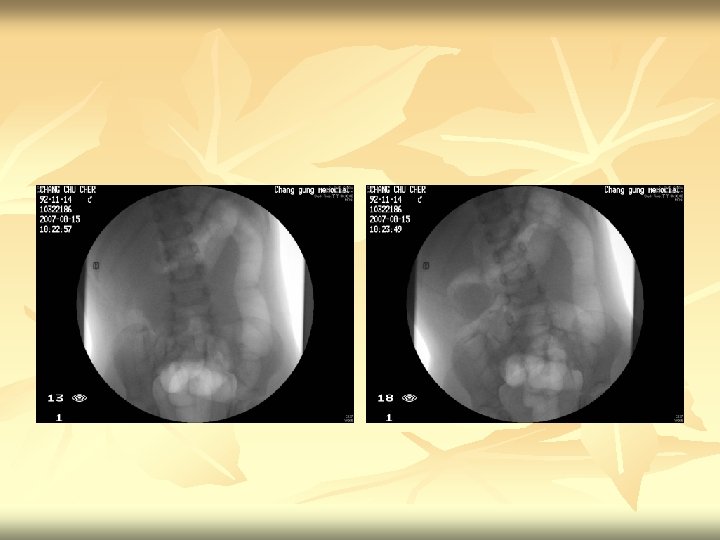

Air reduction

Fluoroscopic reduction of intussusception n n 1. Preliminary radiograph shows soft tissue density at hepatic flexure of the colon compatible with intussusception. 2. Under pressure-device monitoring, air reduction was attempted. 3. Free reflux of air into the terminal ileum was noted, indicating successful reduction. 4. Post-procedural standing radiograph shows no free air in the peritoneum. Impression : Intussusception, ileocolic, successful reduction.